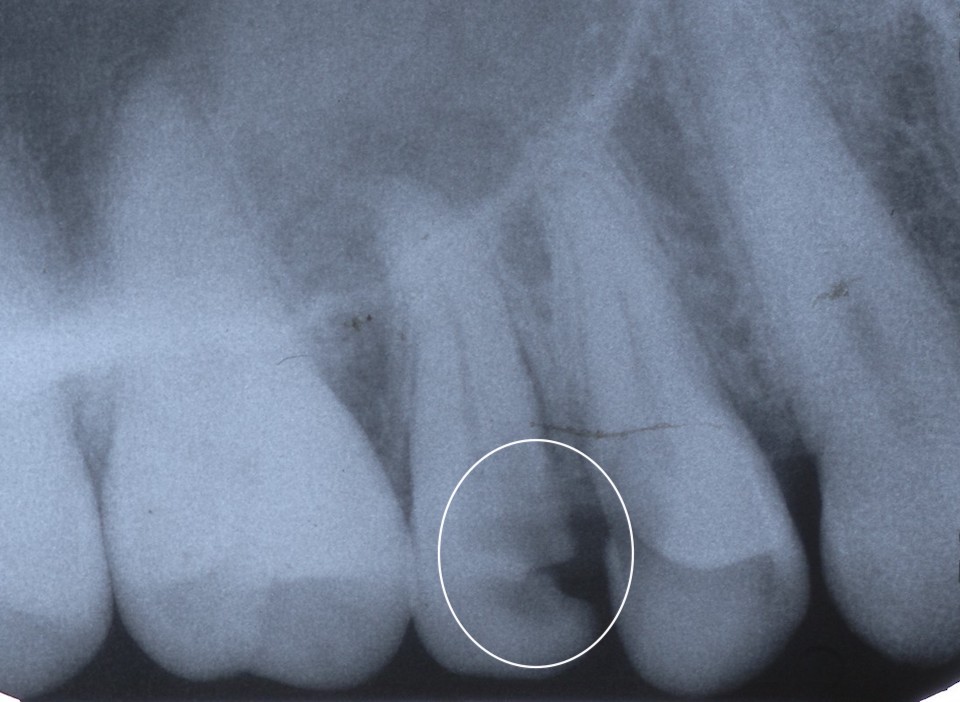

下顎7番の頬側歯茎部カリエスの原因 2025.06.04